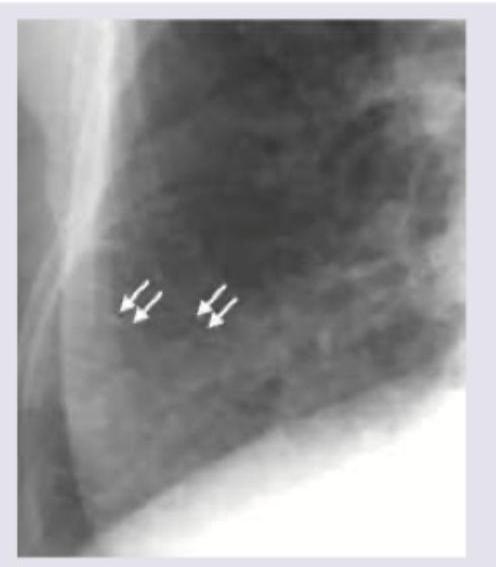

The CXR shows markings near the costophrenic angle. Which of the following is the cause of these markings? (Recent NEET Pattern 2016-17)

Explanation: ***Lymphangitis carcinomatosis*** - The image shows **reticulonodular interstitial markings** with preserved lung volumes, particularly prominent near the costophrenic angle, which are classic for **lymphangitis carcinomatosis**. - This condition is caused by the infiltration of **malignant cells into the lymphatic channels** of the lung, leading to thickening of the interlobular septa and a characteristic radiographic appearance. *Pulmonary alveolar proteinosis* - This condition typically presents with diffuse ground-glass opacities and consolidation, often described as a **"crazy-paving" pattern** on CT, which is not seen here. - It involves the accumulation of lipoproteinaceous material within the **alveoli**, rather than lymphatic infiltration. *Lung abscess* - A lung abscess would appear as a **cavitated lesion** with an air-fluid level, indicating necrosis and fluid accumulation, which is distinctly different from the interstitial markings in the image. - It is typically caused by **bacterial infection** and is a focal process, not diffuse interstitial infiltration. *Pneumatocele* - A pneumatocele is a **thin-walled, air-filled cyst** commonly seen after pneumonia in children or trauma, appearing as a clear, defined space on imaging. - It does not present with the diffuse reticulonodular pattern or interstitial thickening characteristic of the image.